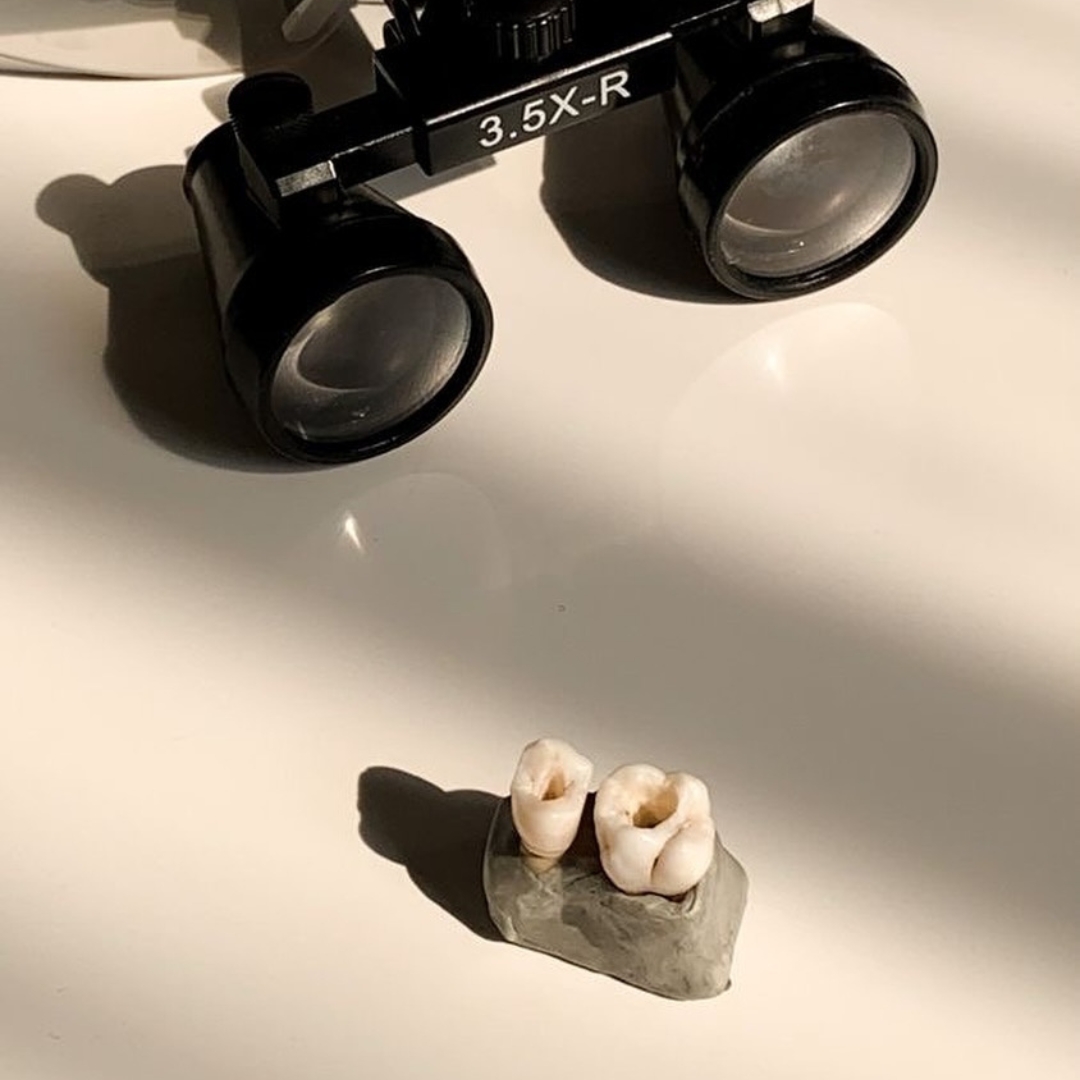

We place implants using guided surgery

This digital planning reduces error margins and enables minimally invasive surgery without extensive incisions. This translates to shorter intervention times, faster recovery, and a more comfortable experience for the patient.

Unlike conventional surgery, guided surgery optimises precision and reduces risks, allowing us to place implants with maximum safety and efficiency. With this technology, we achieve predictable and aesthetic results, ensuring functionality and well-being from day one.